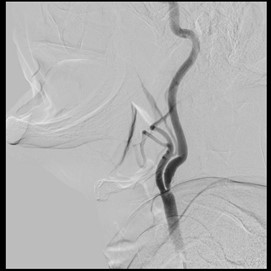

El paciente fue llevado a procedimiento endovascular con colocación de stent carotídeo izquierdo presentando recanalización de flujo en porcion obstruida arteria carótida interna izuiqerda (figura 2) y continuando terapia farmacológica con aspirina, clopidogrel y estatina. Presentó recuperación completa de los síntomas verificado en el último control a los 2 meses del episodio.

Figura 2A . Angiografía Cerebral: Stent a nivel de porción obstruida de carótida interna izquierda. B. Angiografía Cerebral: Recanalización de flujo posteior a Stent en carótida interna iziquerda.